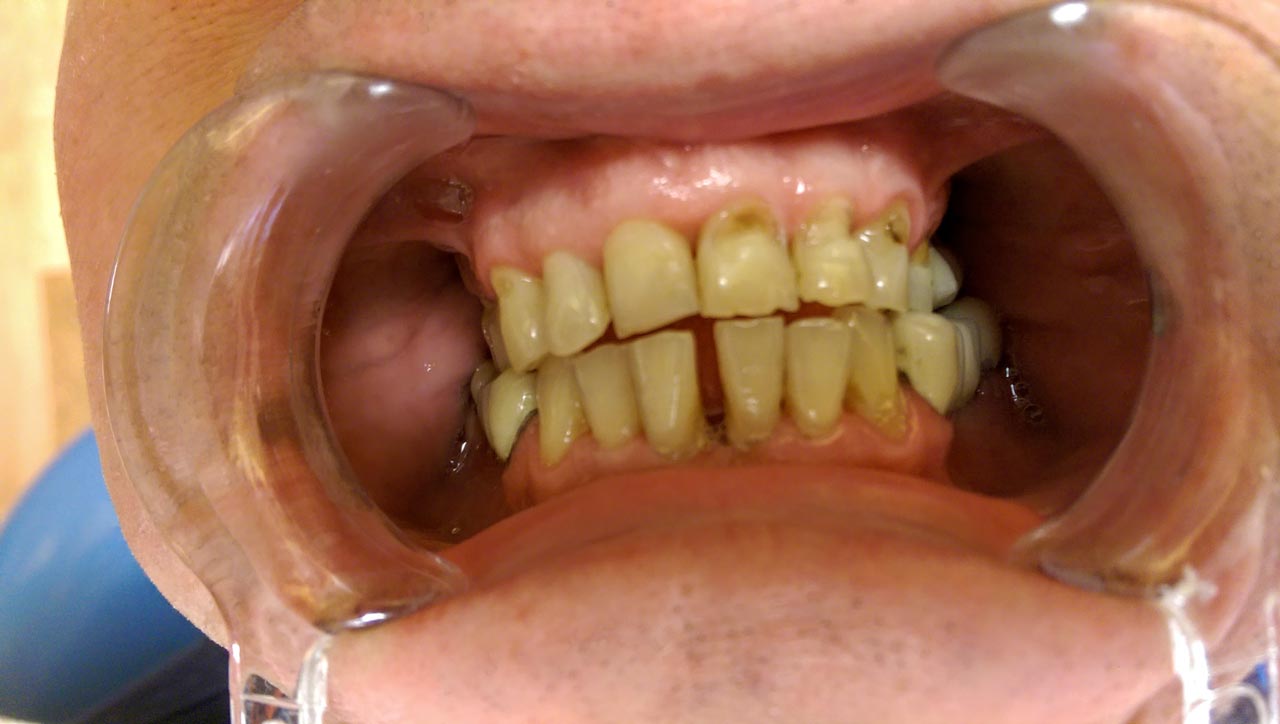

Fogmegtartó kezelések

Amennyiben pácienseink rendszeresen részt vesznek az éves szűrővizsgálaton, az esetek jelentős részében elkerülhetőek a foghúzások, szájsebészeti komolyabb beavatkozások, és csupán apróbb kezelésekre lehet szükség! Ilyenek például a szájhigiéniás kezelések, esztétikus tömések, betétek, koronák, gyökérkezelések.

Betegeink többféle (kémiai kötésű és fényre kötő) esztétikus tömés közül orvosainkkal együtt választják ki a megfelelőbbet! Fémmentes betéteinkkel, koronáinkkal természethűen tudjuk visszaállítani fogazatát. Gyökérkezeléseket csúcstechnológiás gépi tágítóval végezzük, aminek segítségével milliméter pontosan tudjuk bemérni a gyökértöméshez a csatorna hosszát.